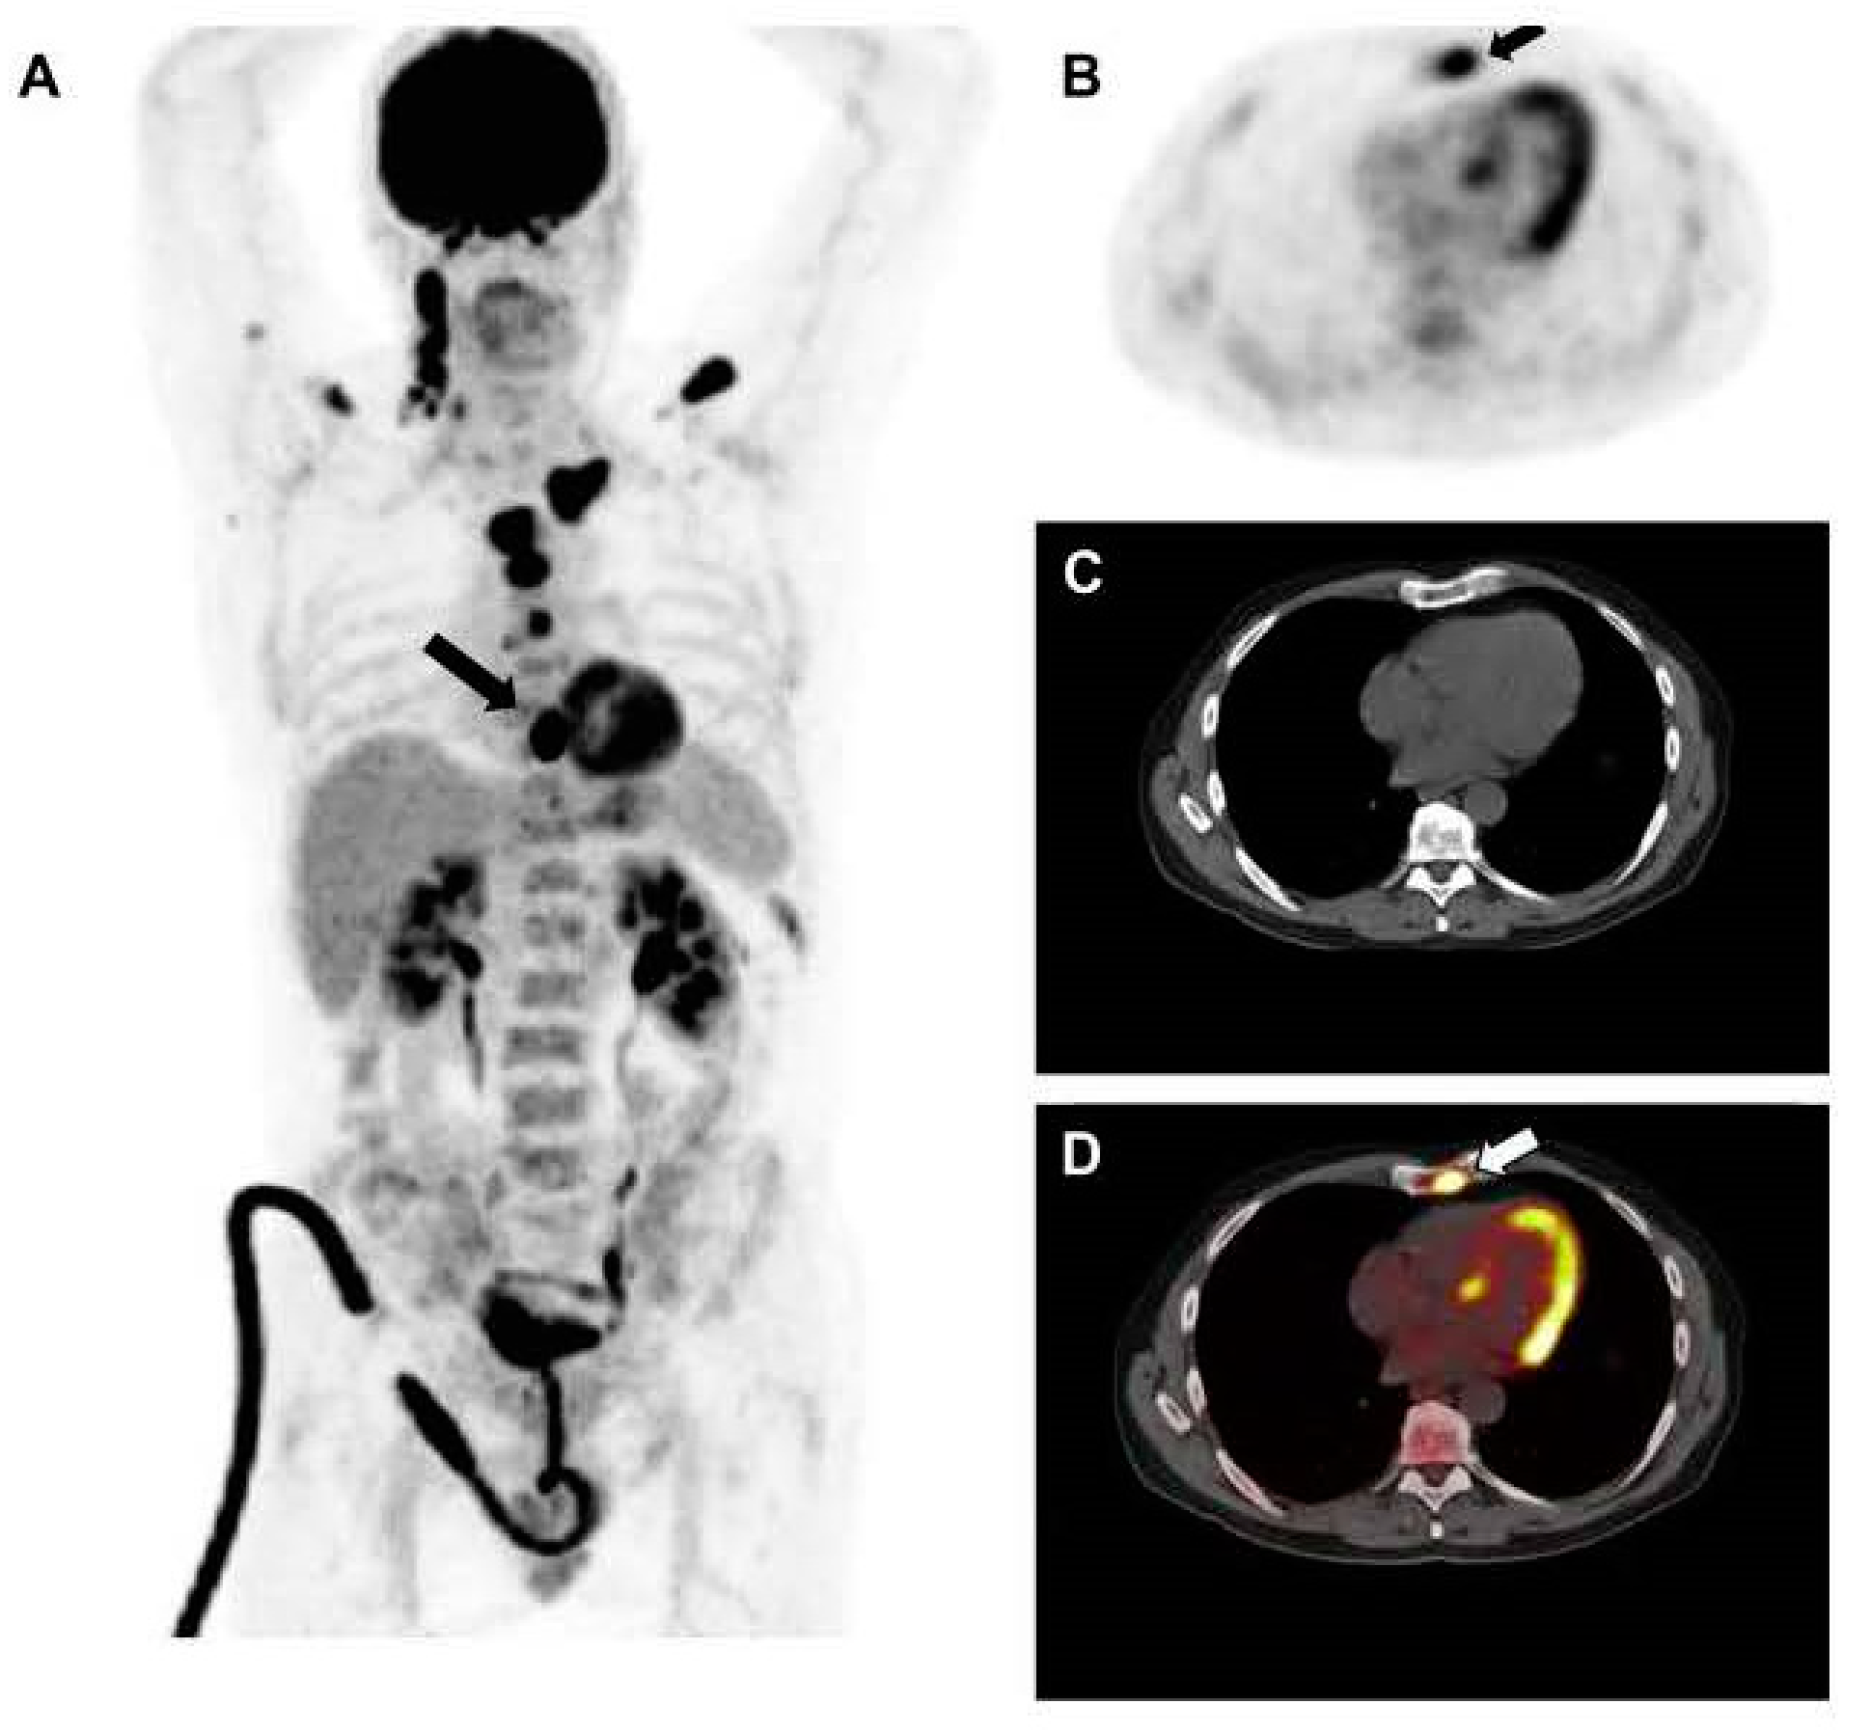

Figure 2.

This figure illustrates the crucial role of [18F]FDG PET in evaluating skeletal disease in MM. The case is of a 60-year-old man newly diagnosed with MM. [18F]FDG PET revealed cervical lymphadenopathies and multiple active lesions with varying degrees of [18F]FDG uptake in the skeleton (A). An active lesion in the sternum (indicated by arrows) was detected on PET and PET/CT (A,B,D), but was not clearly visible on CT alone (C). The image was sourced from PMID: 31084774 (Figure 1), and permission was granted for its use.